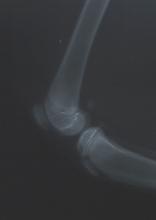

De diagnose is te stellen door een dierenarts die de op de hoogte is van de bouw van een kniegewricht. De patella is met duim en wijsvinger vast te pakken en zo kan er worden nagegaan of er een abnormale beweeglijkheid aanwezig is. Mogelijk kan ook een stationaire patellaluxatie worden vastgesteld.

Met behulp van röntgenfoto's is ook de oorzaak van de patellaluxatie vast te stellen.

Zo kunnen diepte van de groeve, de hoek van het kniegewricht en de belijning van het dijbeen zichtbaar worden gemaakt en worden gemeten. In het dierenziekenhuis te Dordrecht worden deze metingen altijd voor de operatie verricht om de operatietechnieken er op aan te kunnen passen.

De sleuf in het bovenbeen is hier te beoordelen. |

gezonde knie | artrotische knie tgv patellaluxatie |